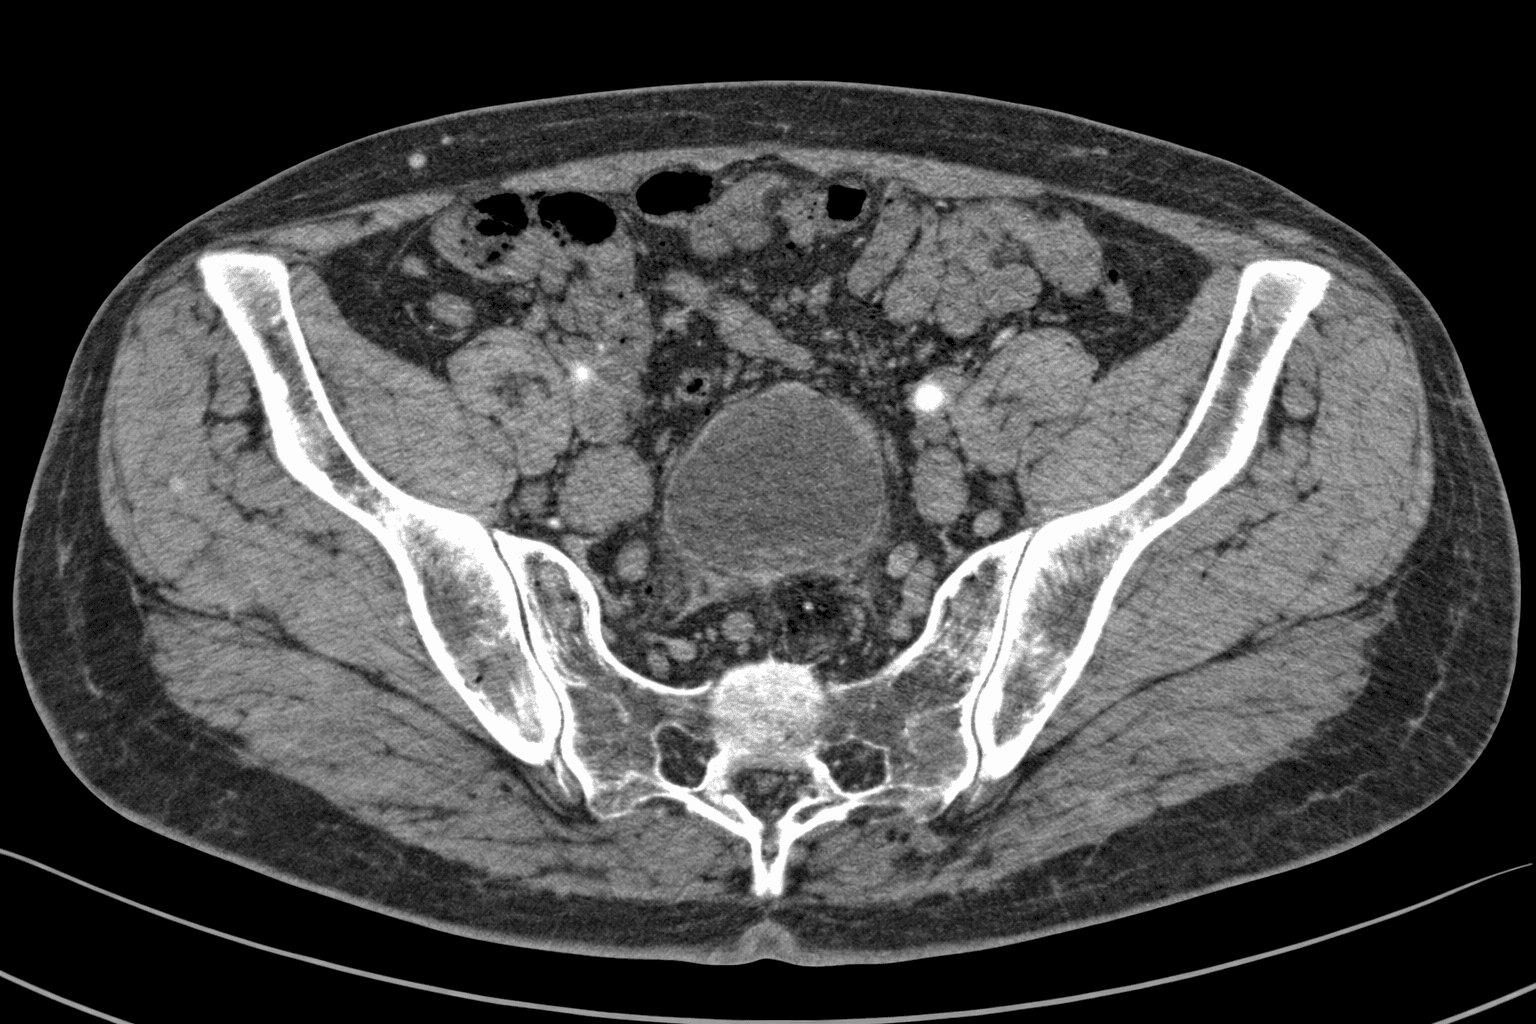

Secure your health with a Lower Abdomen CT Scan! The importance of early diagnosis with our modern medical imaging center services, accompanied by expert radiologists. Click for check-up packages!